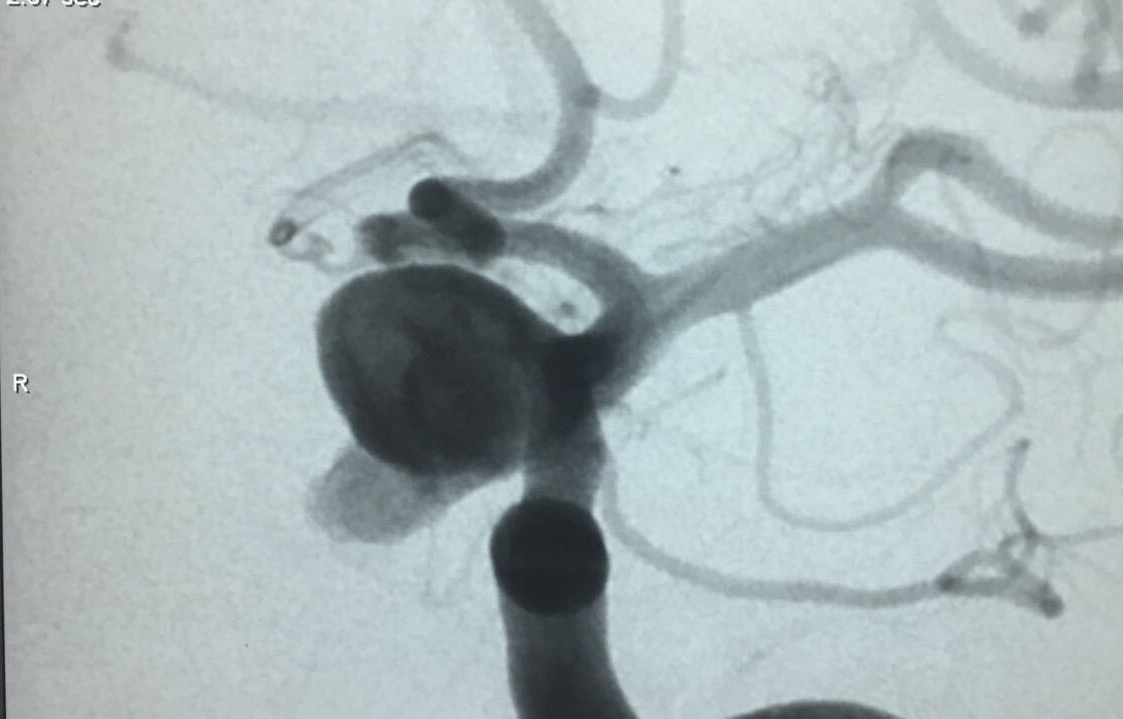

Aneurisma de topo da carótida

SNA. 76 anos . Durante investigação ambulatorial de cefaléia e tremor nas mãos foi realizado Angiotomografia de crânio evidenciando aneurisma incidental em topo da...